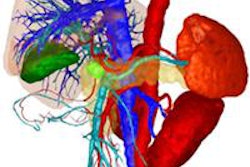

Based on extensive imaging workup and patient clinical status in cases of colorectal liver metastases, radiologists and hepatobiliary surgeons must discuss whether the patient is resectable, unresectable, or borderline. In unresectable or borderline patients, radiologists should evaluate tumor response to select the best treatment. In the future, morphologic and functional imaging may anticipate the histologic response.

"In colorectal liver metastases, the main goals are to assess resectability, to consider secondary resectability, and to evaluate tumor response," he said. "CT and MR imaging are essential, MR being the most sensitive for tumor detection. Further work has to be done to better analyze tumor response using functional imaging."